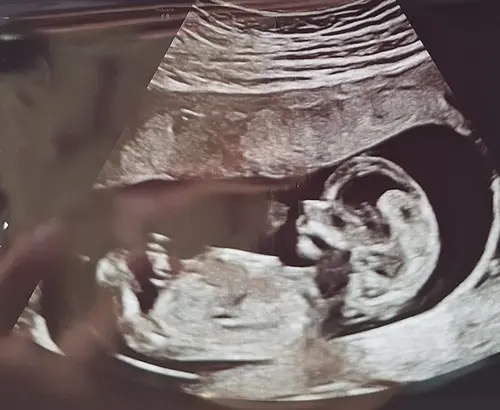

We hebben vandaag een hele mooie 13-weken echo gehad. Het kindje doet het heel goed.

Volgens chat gpt is het 95% zeker een meisje, maar ik wacht nog even tot de geslachtsecho 19 juli om het zeker te weten.